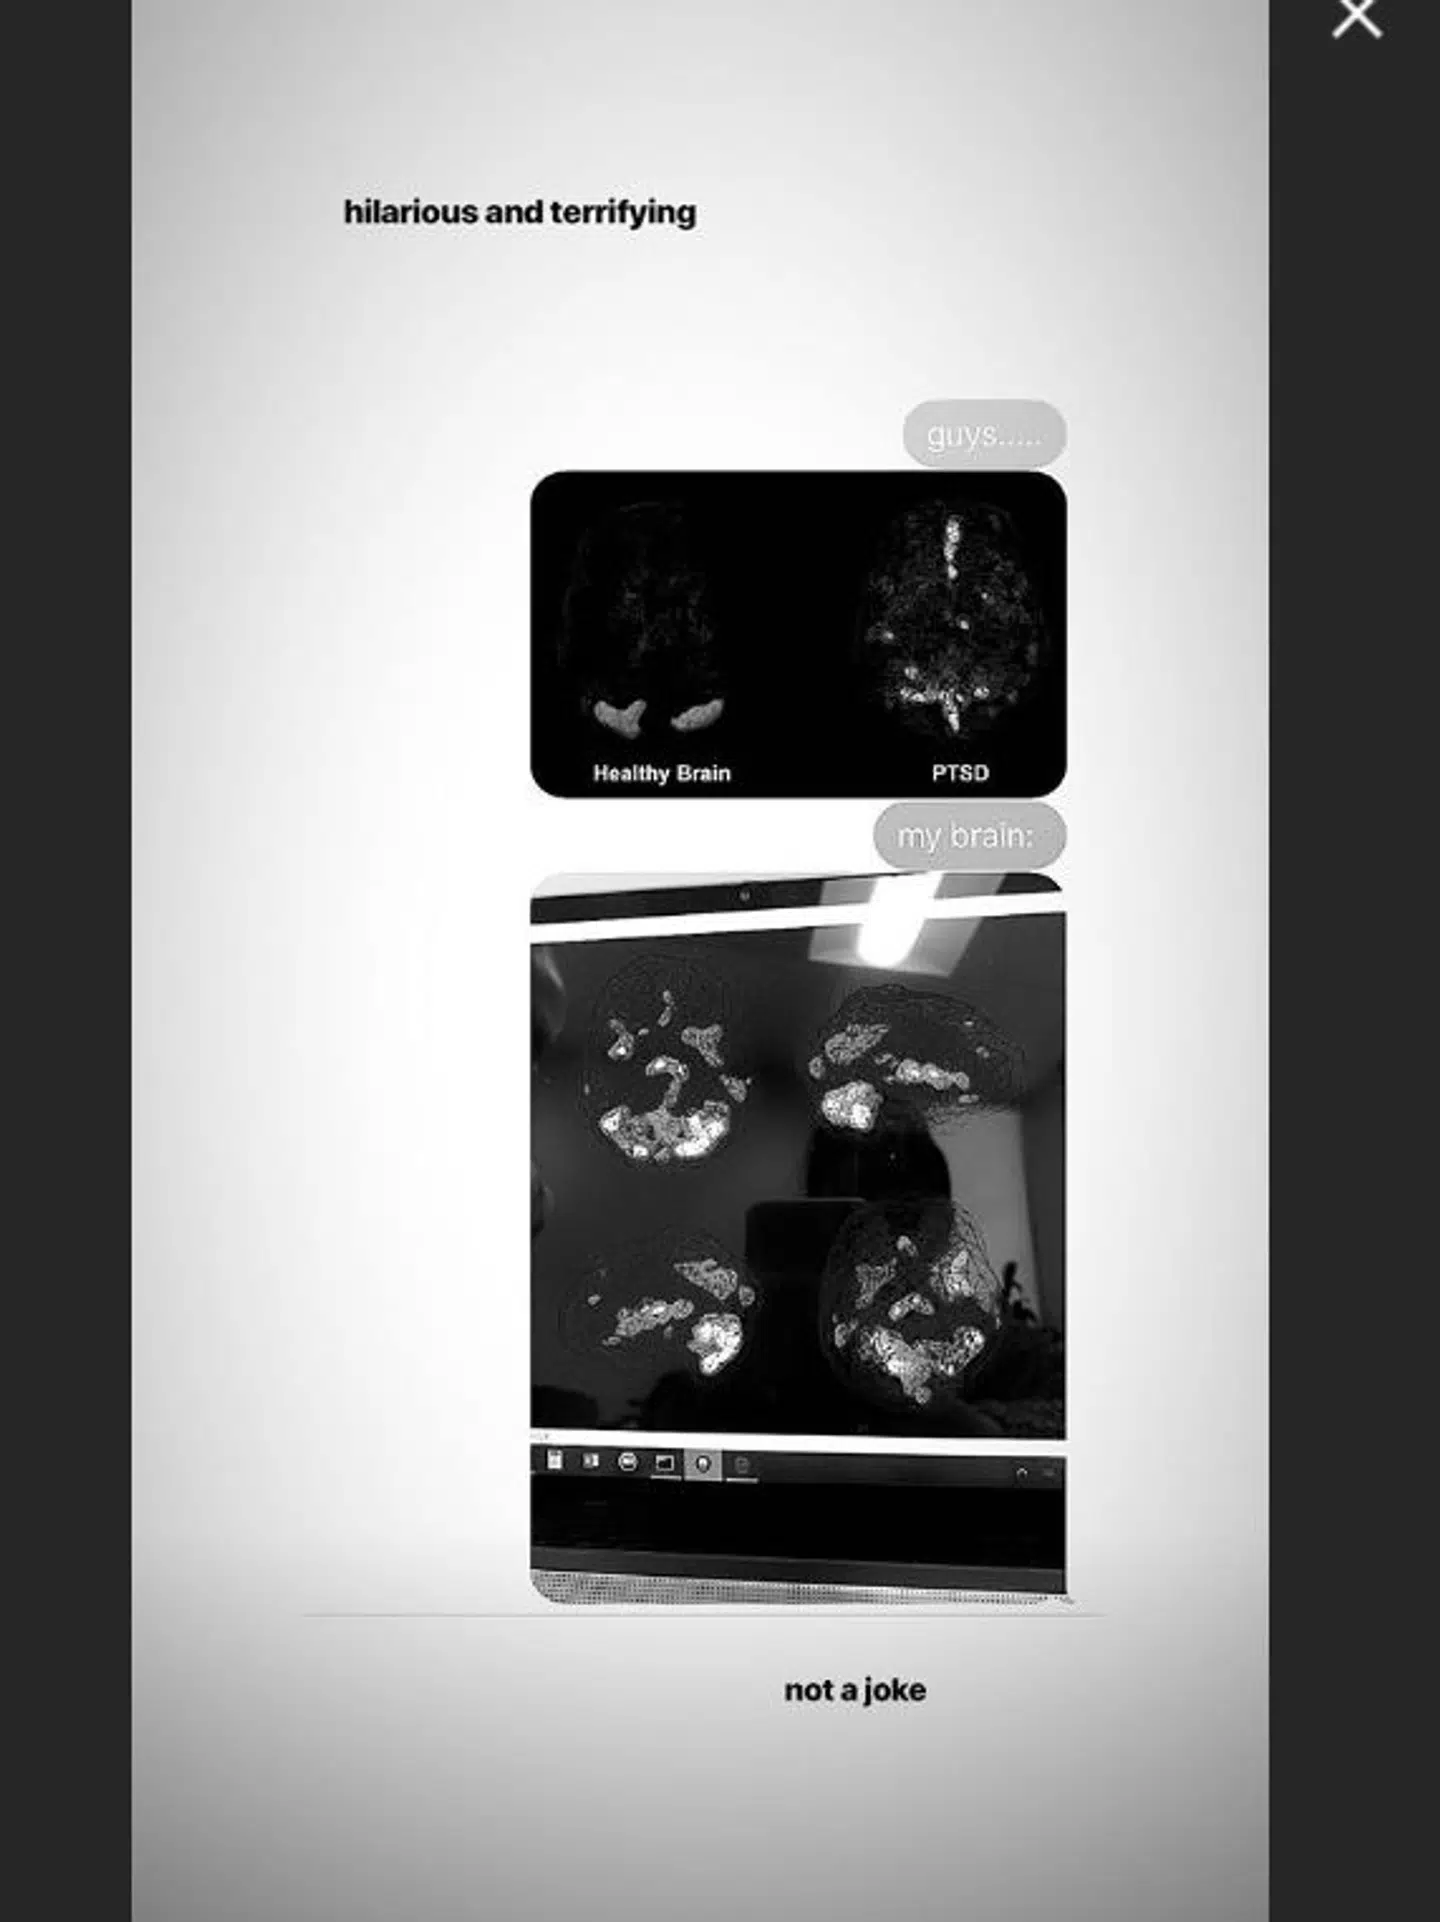

Hun deler et scanningsbillede af sin hjerne, som den ser ud i dag.

Øverst ligger der så scanninger af en 'almindelig' hjerne sammen med en hjerne tilhørende én, der lider af PTSD.

Nedenunder kan man så se Grandes skanningsbilleder, som ligner hjernen med PTSD.

Han fortæller, at Ariana Grande viser tydelige tegn på det diamant-formede mønster, som er karakteristisk for folk med PTSD.